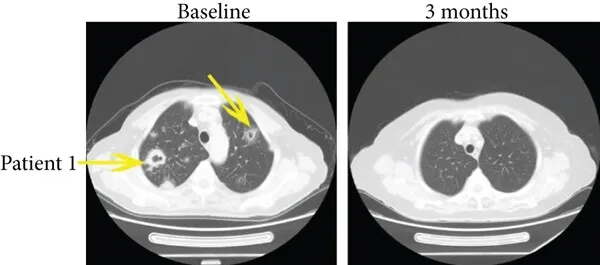

病例1为一例35岁患者,治疗前伴随肺转移,接受免疫联合治疗3个月后,多发性肺转移灶完全消失(详见下图,黄色箭头所示),PFS达15.4个月。

▲图源“J Immunol Res”,版权归原作者所有,如无意中侵犯了知识产权,请联系我们删除